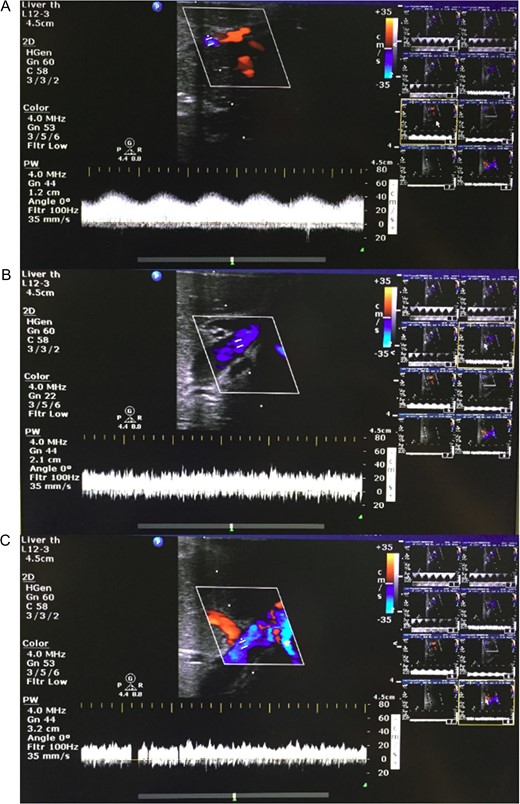

Flow parameters and perfusate analysis were recorded throughout splitting from left and right hepatic arteries, portal veins and IVC. Post-procedure blood flow was confirmed using Doppler ultrasound (CX50 CompactXtreme, Philips, The Netherlands), in each lobe.

Post-hilar phase lactates were similar in both hepatic arteries, portal veins and IVC (Table 1). Post-parenchymal phase lactate was unchanged. IVC Lactate increased by 0.3 mmol/L compared to the pre-hilar phase. Bile production continued throughout. Doppler ultrasound demonstrated expected hepatic arterial, portal venous and IVC waveforms in both lobes after splitting (Fig. 3).

Representative Doppler ultrasound images of parenchyma from liver split with concurrent NMP-L. (A) Hepatic arteriolar waveform; (B) portal venous waveform; and (C) hepatic venous waveform.